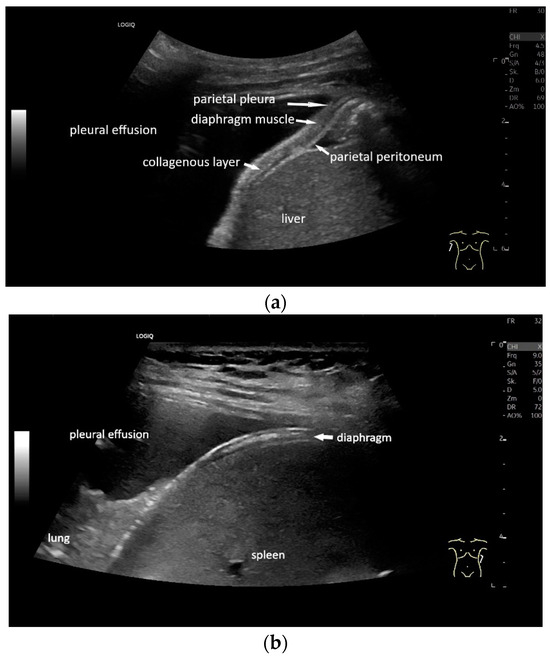

With high-resolution linear transducers, the diaphragm presents itself as a hypoechoic band. It is covered on both sides by a very thin hyperechoic layer. This corresponds to the peritoneum and the parietal pleura, respectively. Depending on the resolution, a further delicate hyperechoic layer is usually visible centrally in the muscle, which is most often considered to be a fibrous layer in the center of the diaphragm (Figure 1).

Lateral transducer position in the zone of apposition: The transducer is positioned longitudinally and laterally in the area of the mid-axillary line or slightly ventral to it between the anterior and mid-axillary lines, approximately in the 8th or 10th intercostal space. The diaphragmatic reflex is located on the inner side of the ribs below the pulmonary glide with pulmonary reverberations. This localization of origin of the diaphragm from the inner side of the rib cartilage is referred to as the zone of apposition (Figure 3). As this localization is only a few centimeters below the skin surface, high-resolution linear transducer use is highly recommended. In this position, the diameter of the diaphragm is measured during inspiration and expiration [2,3,4,5] (Figure 4). The thickness of the diaphragm varies, with caudal parts being thicker than cranial parts. The measurement of diaphragm thickness is highly variable depending on the intercostal space chosen, with thickness varying by up to 6 mm between the intercostal spaces [6]. It is therefore important to select the same position for comparable measurements and, if necessary, to mark the location for the transducer position [7]. Obesity limits assessment of the diaphragm [2].